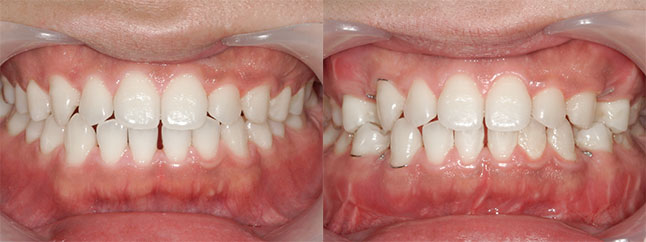

大阪府 19歳 男性

執刀医 辻和志

【治療内容】上下セットバック…上のアゴと下のアゴの両方が前に出ていた為、上下のアゴの骨を切って後ろに下げました。

【費用】上下セットバック 2,307,800円(税込)

【リスク】全身麻酔で行うため全身の健康状態が悪い方は行うことができません。また、手術当日は安静にしていただく必要があります。